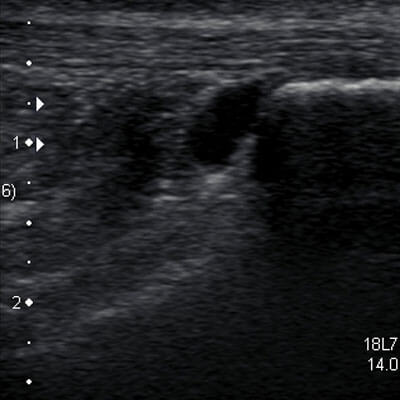

Imaging of the Foot and Ankle

Ultrasound is beneficial in diagnosis of soft tissue injuries including Plantar Fasciitis, Achilles Tendinopathy, Forefoot pathology, Ankle sprain